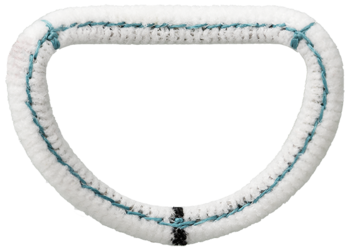

SÉGUIN

THE SÉGUIN™ SEMI-RIGID RING HAS A UNIQUE COMBINATION OF RIGIDITY AND FLEXIBILITY

The Séguin™ Semi-Rigid Ring provides surgeons with a combination of rigidity and flexibility for mitral valve repair.

- Semi-rigid, tri-dimensional posterior designed to preserve the physiologic motion of the annulus

- More rigid anterior allows for annular remodeling

- Solid one-piece core resists needle penetration and reduces potential for suturing through the core

FLEXIBILITY IN JUST ONE STEP

The design advantage of the Séguin™ Semi-Rigid Ring delivery system is that it employs a one-step process designed to save time and reduce complexity during surgery.